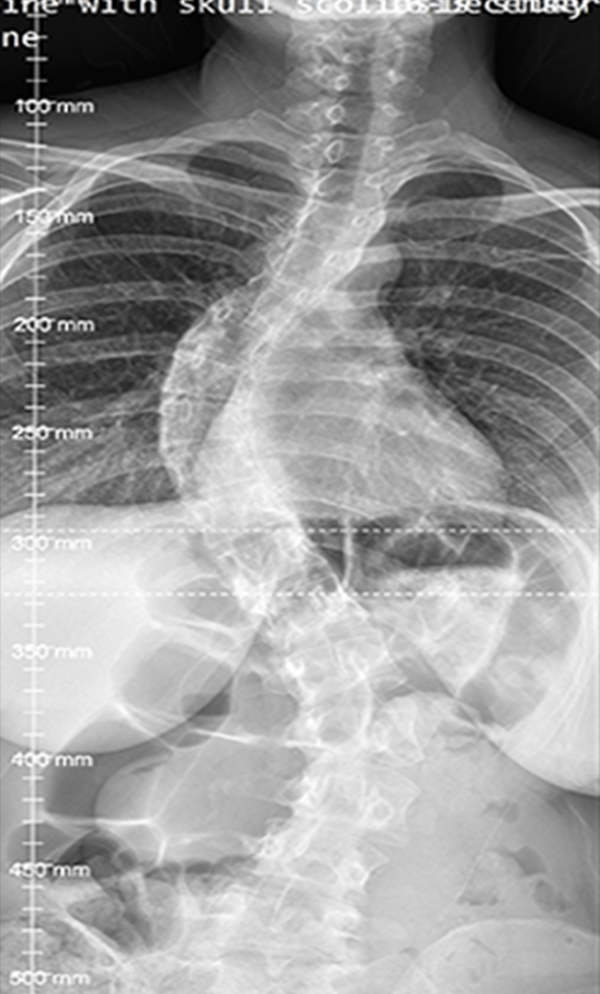

Gallery : Before - After